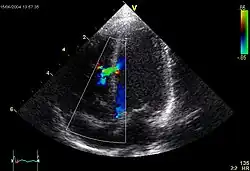

A VSD can be detected by cardiac auscultation. Classically, a VSD causes a pathognomonic holo- or pansystolic murmur. Auscultation is generally considered sufficient for detecting a significant VSD. The murmur depends on the abnormal flow of blood from the left ventricle, through the VSD, to the right ventricle. If there is not much difference in pressure between the left and right ventricles, then the flow of blood through the VSD will not be very great and the VSD may be silent. This situation occurs a) in the fetus (when the right and left ventricular pressures are essentially equal), b) for a short time after birth (before the right ventricular pressure has decreased), and c) as a late complication of unrepaired VSD. Confirmation of cardiac auscultation can be obtained by non-invasive cardiac ultrasound (echocardiography). To more accurately measure ventricular pressures, cardiac catheterization, can be performed.

Intraoperative transesophageal echocardiography is used to confirm secure closure of the VSD, normal function of the aortic and tricuspid valves, good ventricular function, and the elimination of all air from the left side of the heart.